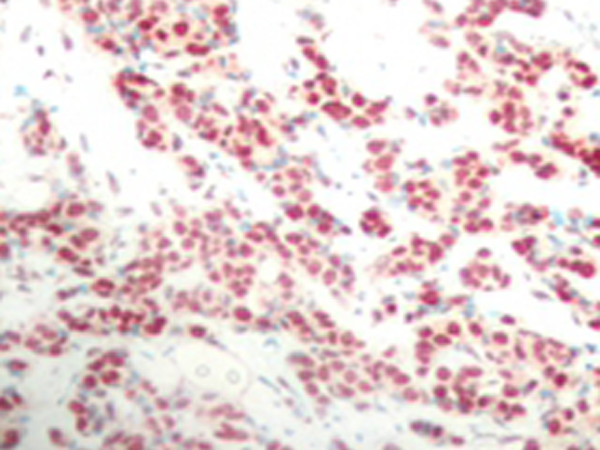

IHC positive control: |

Human breast carcinoma tissue |

IHC Recommend dilution: |

50-100 |